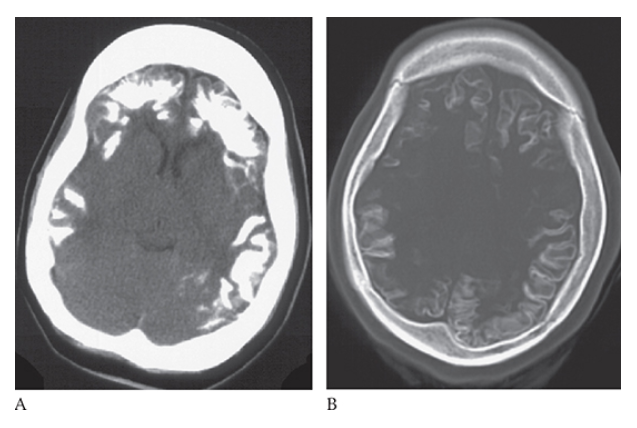

What is A

Sturge-Weber Syndrome. Noncontrast CT images of the brain and bone window

What is B

Sturge-Weber Syndrome. Noncontrast CT images of the brain demonstrate bilateral frontal and parietal cortical calcifications.